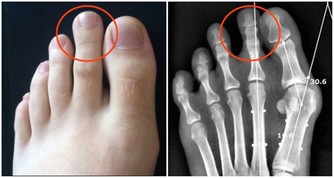

10、 用手推入:有時候,痔瘡指的是肛門內膜向外突出,而非靜脈腫大。假使你出現這種外突性痔瘡,不妨試著將它推回肛門內,垂在外面的痔瘡容易演變成血塊。